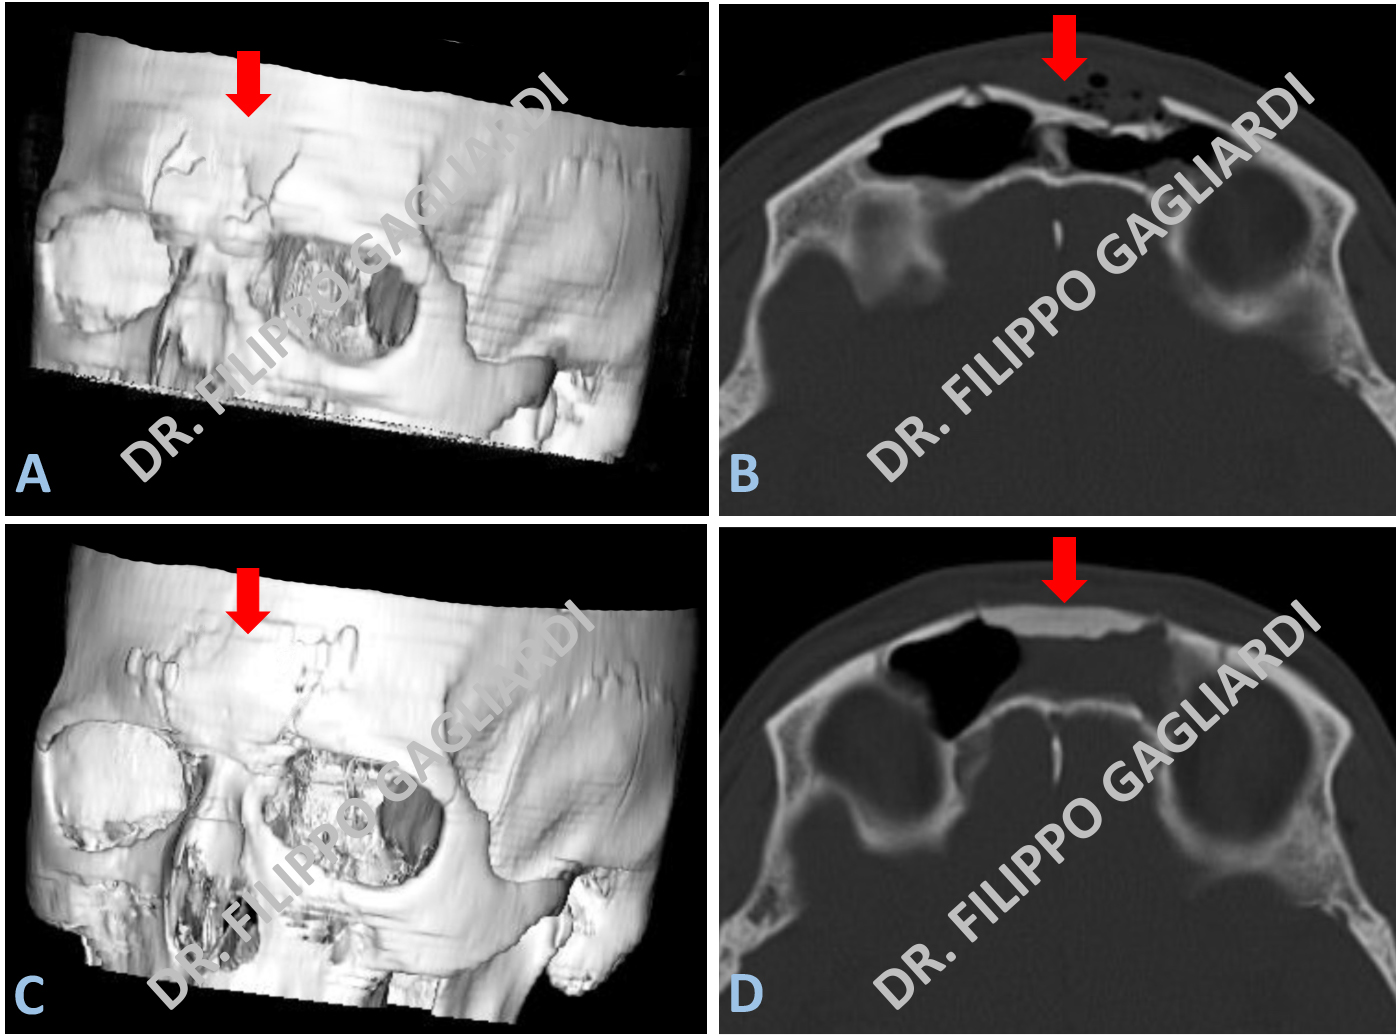

Cranioplastica per frattura del seno frontale

Esempio di cranioplastica in un caso di frattura pluriframmentaria post-traumatica della parete anteriore del seno frontale (cavità all’interno dell’osso frontale in comunicazione con le cavità nasali). La Figura A mostra la ricostruzione tridimensionale della frattura. Nella Figura B si può vedere l’immagine TC in sezione assiale della nota frattura. La Paziente è stata sottoposta ad intervento chirurgico di cranioplastica in materiale eterologo. È stata eseguita la ricostruzione anatomica della parete ossea, come dimostrato dalla ricostruzione tridimensionale (Figura C). La Figura D documenta gli esiti di intervento alla TC post-operatoria.